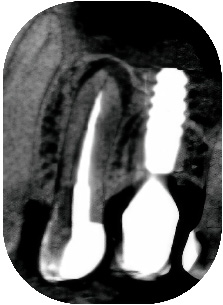

prémolaire, la corticale sous-sinusienne est intacte.Fig. 03 : Ia corticale sous-sinusienne

est intacte.

prémolaire, la LIPOE Fig. 04 : le canal vestibulaire est totalement oblitéré, sans signe d’infection visible.